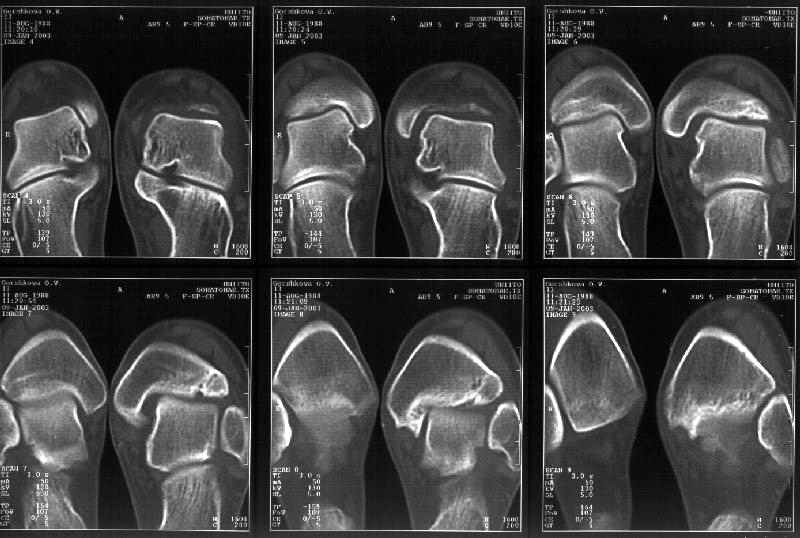

Я пометил линию перелома черной линией.

К сожалению на последних присланных срезах КТ нет более низкого, через таран, среза, который был на прежнем майле. На XR я попытался показать

стержень внутри сустава и то как он раскрывает пространство между тараном и мед. малеолом.

Сегодня пациентке сделали сравнительную КТ. А ксиальные и Фронтальные срезы приложены. Ваше мнение?

Фронтальные

Аксиальные

Отправитель: Й. Воск 19 Январь 2003, 22:50

На КТ я попытался изобразить скромными своими способностями (А)- место перелома, (С)- нормальный суставной зазор меж тараном и тремя его маллеолами. (В)- образовавшийся в результате перелома широкий раза в три зазор, позволяющий, по-моему, сублюксацию тарана при ходьбе. В свете данных КТ, критически важных, я бы предложил вертикальную остеотомию места перелома

задне-внутренним подходом и фиксацию мед. маллеола прижатым к тарану с помощью тонкого compression screw. После этого гипсовый сапожок и немедленное расхаживание ноги.